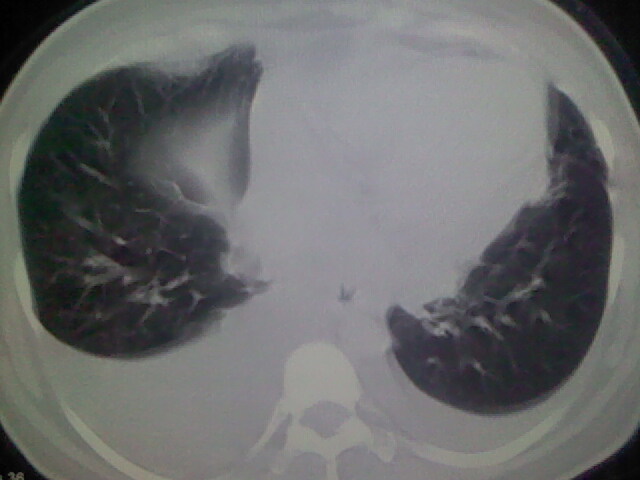

女,24,剖腹产后,突觉胸痛,干咳,不能平卧

胸水 感染 心影增大 肺水肿?

双肺“肺泡性肺水肿” “胸腔积液”!

双侧胸腔积液,肺泡性肺水肿。后纵隔好像有占位。

考虑肺梗塞、肺水肿,双侧胸腔积液

肝脾大,双侧胸腔积液,双肺水肿,肺动脉[包括远端小动脉],左右心房,左心室增宽,右心室主动脉无明显改变,符合左心功能不全征;;建议除外二尖瓣关闭不全,扩张性心肌病